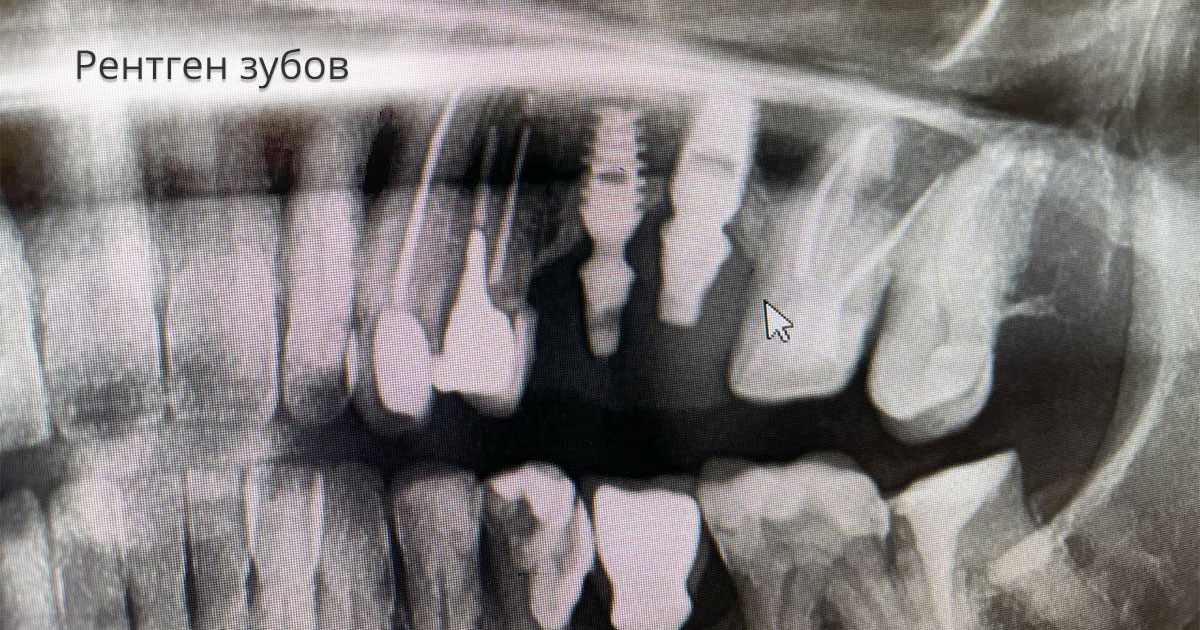

Рентгеновские технологии: усиленные экраны 35x35